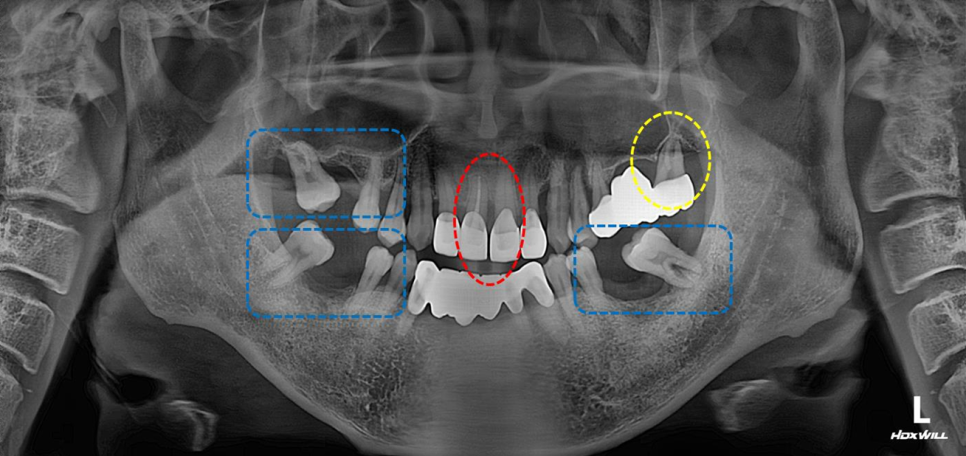

빨간색 : 보철 후 앞니가 벌어짐

노란색: 치조골이 녹아서 잇몸상태가 좋지 않음

파란색: 발치 후 방치하여 어금니가 쓰러짐

위 설명처럼 여러가지 문제가 보입니다.